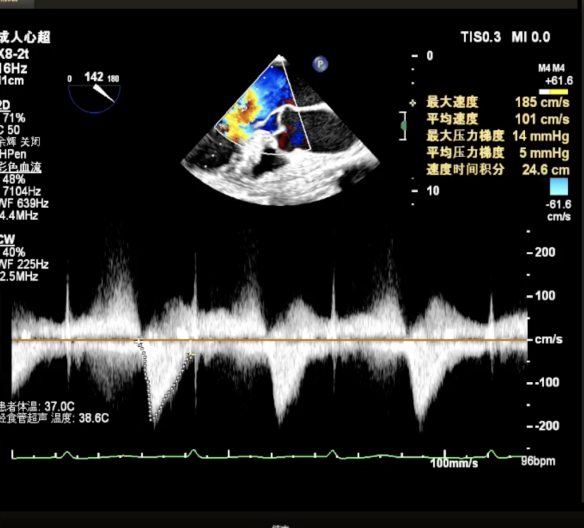

Vmax=185cm/s 平均跨瓣压差为5mmHg

PW显示左肺静脉内收缩期可见逆流信号